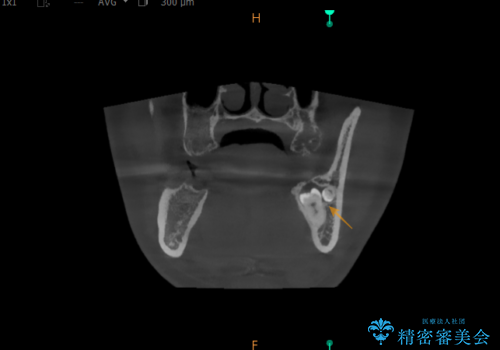

【埋伏智歯と埋伏智歯の過剰歯の抜歯】埋まっている親知らず2本の抜歯の症例写真

【埋伏智歯と埋伏智歯の過剰歯の抜歯】埋まっている親知らず2本の抜歯